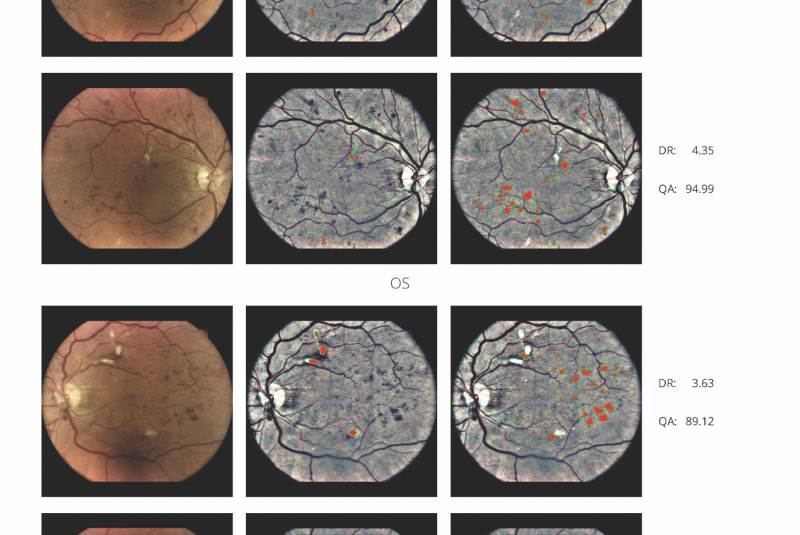

Kamera iCare DRSplus společně pomocí softwaru využívajícího umělou inteligenci Thirona RetCAD™ provádí vyhodnocení screeningu diabetické retinopatie, která šetří váš drahocenný čas, umožňuje včasnou intervenci a pomáhá poskytnout včasnou zdravotní péči. Anlýza pomocí Thyronu RetCAD™ nenahrazuje vyšetření zdravotního stavu očí.

Zpráva obsahuje

- stupnici závažnosti onemocnění pro diabetickou retinopatii

- v případech kdy je to nutné, AI doporučuje poslat pacienty na další vyšetření ke specialistovi

- infračervené mapy zvýrazňující světlé a červené léze/poškození

- hodnocení kvality vstupních obrázků